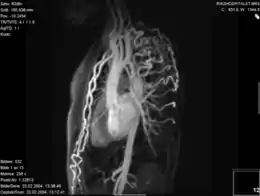

Selected image –